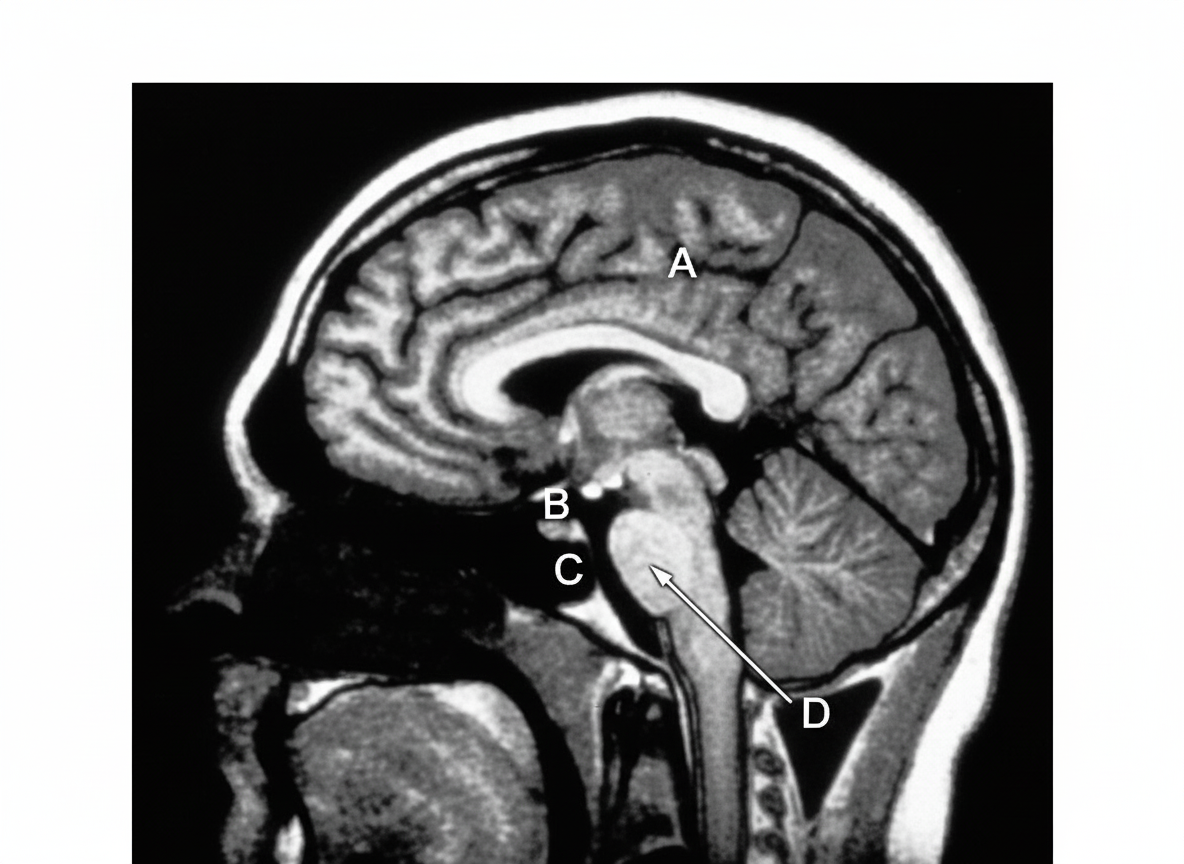

T1 weighted MRI of midsagittal section of the brain is shown. Which among the marked structures contains the two lateral foramina of Luschka?

Explanation: ***D*** - The **fourth ventricle** contains the two lateral **foramina of Luschka** in its lateral recesses, which are **lateral apertures** allowing CSF drainage. - Located in the **posterior fossa** between the brainstem and cerebellum, the fourth ventricle is clearly visible on midsagittal MRI. *A* - This structure does not contain the **foramina of Luschka**, which are specifically located in the lateral recesses of the fourth ventricle. - The **lateral apertures** are anatomically positioned in the posterior fossa, not in this marked region. *B* - This anatomical structure lacks the **lateral recesses** where the foramina of Luschka are located. - The **foramina of Luschka** are exclusive to the fourth ventricle and cannot be found in this marked area. *C* - This region does not house the **fourth ventricle** or its associated **lateral apertures**. - The **foramina of Luschka** are specifically found in the lateral recesses of the fourth ventricle, not in this structure.